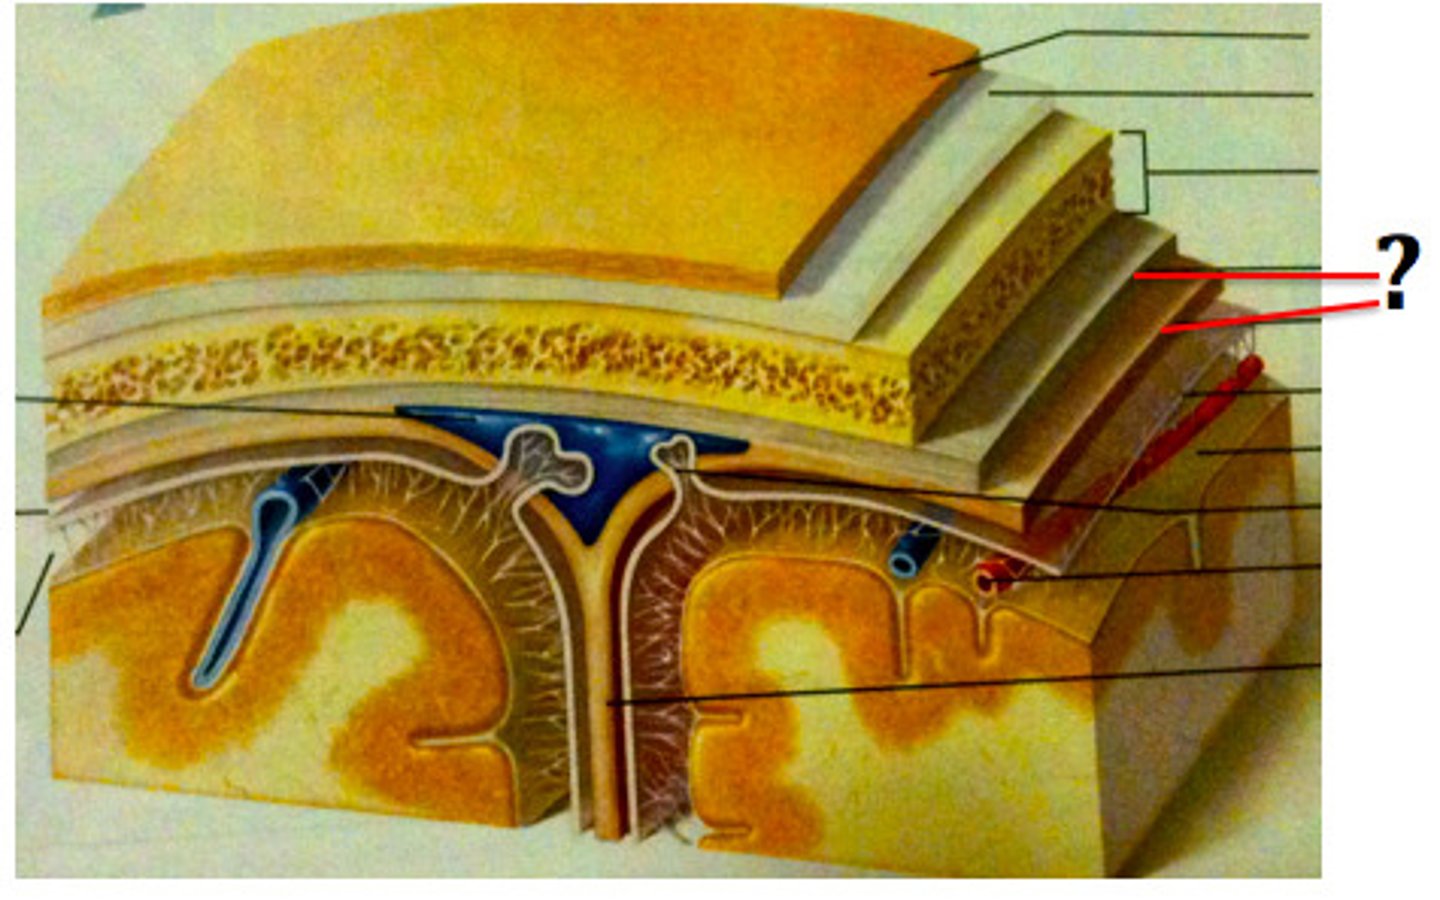

Meninges

-Three connective tissue membranes that envelope the CNS

-Protect the CNS and provide structural framework for its arteries and veins

Meninges Location

-Lies between the nervous tissue and bone

Cranial dura mater

-Outer periosteal

-Inner meningeal

-Folds inward to extend between parts of the brain

Cranial dura mater location

-Layers separated by dural sinuses

-Pressed closely against cranial bones

=No epidural space

=Only attached to bone around foramen magnum, stella turcica, crista galli, and sutures of the skull

Dural sinuses

-Separates layers of cranial dura mater

-Collect blood circulating though brain

Arachnoid mater

-Transparent membrane over brain surface

Subarachnoid space

-Separates arachnoid mater from pia mater below

-Contains CSF

Subdural space

-Separates arachnoid from dura mater above in some spaces

Pia mater

-Very thin membrane that follows contours of brain, even dipping into sulci

-Not usually visible without a microscope

Ventricles

-Internal chambers within the brain

Choroid plexus

-Spongy mass of blood capillaries on the floor of each ventricle

Ependymal

-Type of neuroglia that lines ventricles and covers choroid plexus

-Produces CSF